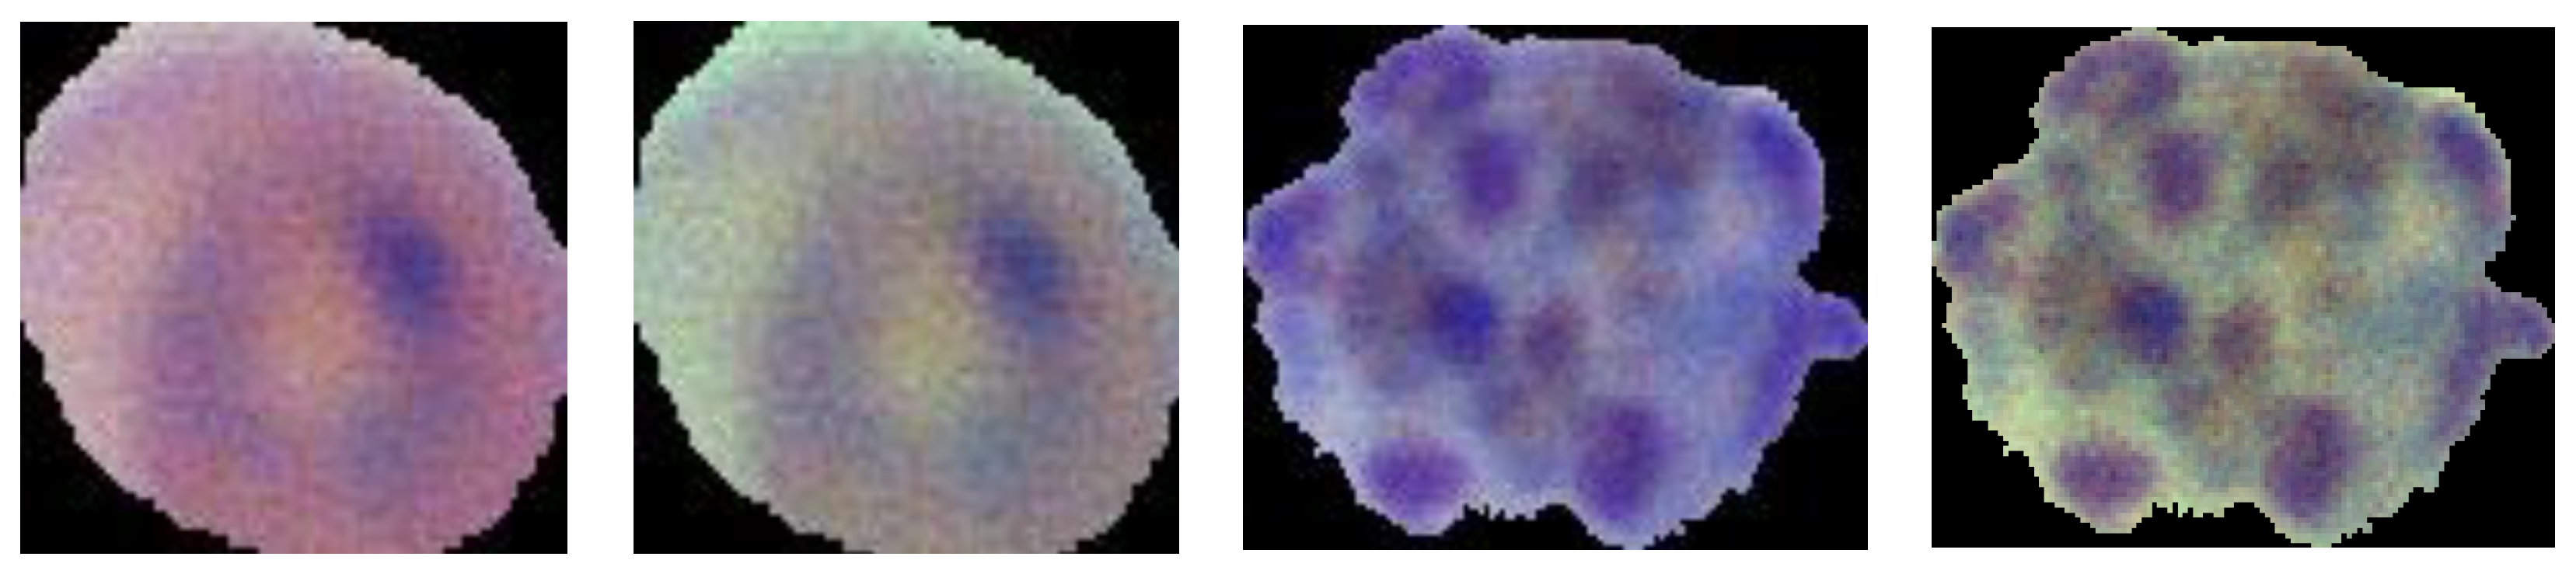

3.1. Datasets

3.1.2. MP-IDB

- Multiclass classification on the MP-IDB-FC dataset (four stages of life);